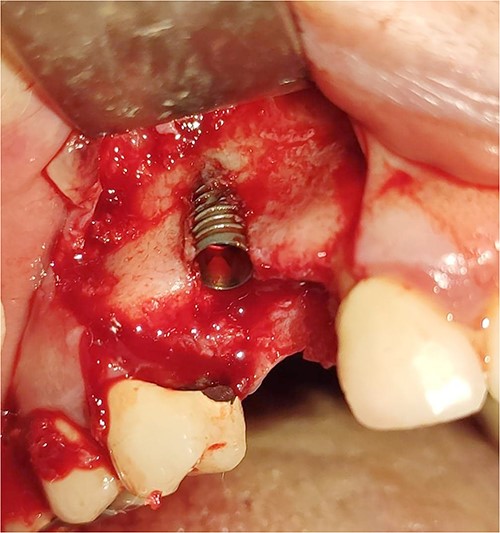

Under local anesthesia with 4% articaine solution, a full-thickness flap was raised to expose the alveolar ridge. The initial point was marked with a point drill. The implant site was first prepared with a 2.2 mm pilot drill, and then with a 3.3 mm drill. After preparing the implant bed, we noticed the disappearance of the coronal and middle third of the buccal wall, exactly as planned. A submerged implant system (INNO submerged implant; Cowellmedi Inc, South Korea) was inserted according to the manufacturer’s instructions (Fig. 1). The insertion torque value was 33 N.cm. several perforations were prepared at the buccal side of the recipient bone bed using a small round bur for better blood supply. An allogeneic bone graft material (Cortical Cancellous powder; TRCIR Co, Iran) was used to reconstruct the buccal plate. A prefabricated L-shaped titanium mesh has been adapted to fit the shape of the alveolar ridge to be reconstructed, and it was fixed to the implant with a cover screw (Fig. 2). The flap was mobilized to permit a tension-free primary closure, was closed with 4–0 silk sutures. Sutures removal was done after 1 week. The surgical sites were left to heal for 6 months.

Reconstruction of the buccal plate using an allogeneic bone graft material and a prefabricated L-shaped titanium mesh. The titanium mesh was fixed to the implant with a cover screw.